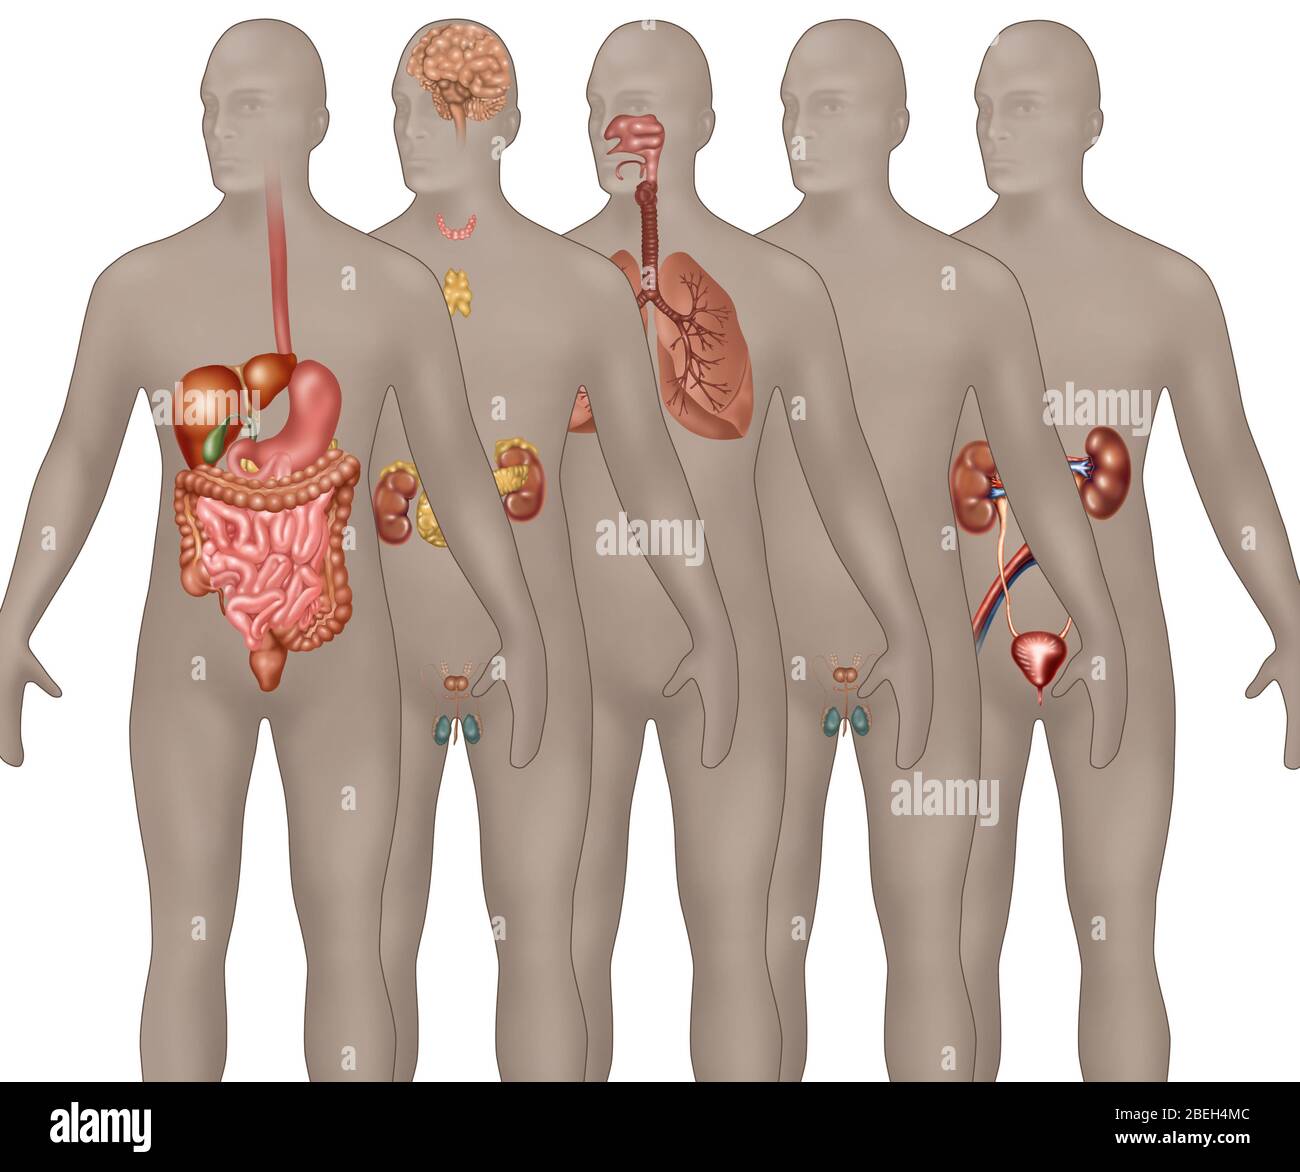

RFPAYTH0–Innere Organe, männlichen Körper - schematische Darstellung der menschlichen Anatomie Illustration - auf weißem Hintergrund.

RFDGYRD7–Männliche Anatomie, inneren Organe allein, volle Atmungs- und Verdauungssystem, mit einigen Organen Cutaway. Anatomie-Bild.